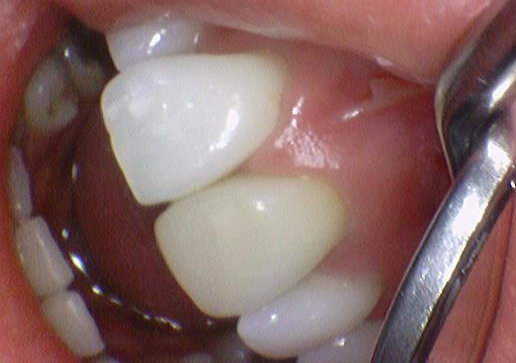

앞니 1개 크라운치료 후

치아를 깎고 임시치아를 끼고 가시고, 다음에 만들어온 크라운을 붙이러 오셨는데요

어금니 크라운과 다르게 앞니 크라운은 모양, 색깔, 특히 색깔의 경우 치아의 색깔이 사람마다 치아마다 매우 다양해서 꼭 색깔 수정가능성이 있다고 설명드리고 들어갑니다.

이 환자분께도 약간 색을 수정할까요 라고 여쭤봤는데

치과 체어에서 크라운을 끼우고 보자마자 색깔이 너무 마음에 든다며 눈물을 흘리셨습니다.

(저희는 한 번 정도 조금 더 자연스럽게 수정하고 싶었어요.

근데 환자분이 너무 마음에 드셔서 보통 앞니의 경우 하는 임시접착도 원하지 않고 바로 영구접착을 원하셨습니다)

앞니 1개 크라운 치료 후